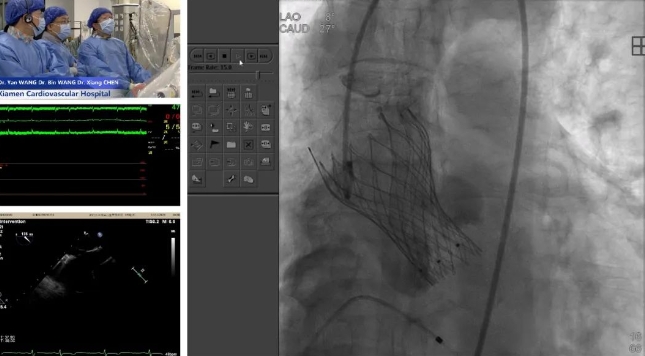

2024-12-18一天两场国际手术直播,华体会体育 助力国产创新器械出海 -